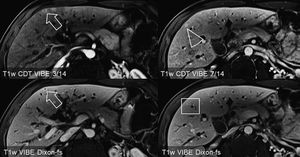

CAIPIRINHA-Dixon-TWIST (CDT) Volume-Interpolated Breath-Hold Examination (VIBE) is a new MR technique for fast Time-Resolved dynamic 3-Dimensional (3D) Imaging of the abdomen with high spatial resolution. The CDT-VIBE allows robust, dynamic contrast-enhanced imaging of the upper abdomen with unprecedentedly high temporospatial resolution. The technique seems suitable for the detection and characterization of focal abdominal lesions such as liver and pancreatic masses. The CDT-VIBE may also prove useful for the acquisition of perfusion measurements in pelvic, breast, and extremity imaging. Figure: Hypervascular hepatic lesions in a 73-year-old man with pancreatic cancer (arrow and arrowhead) depicted clearly with CDT-VIBE. With venous phase VIBE imaging, only the larger metastasis in segment 4b of the liver can be appreciated (arrow, lower row), whereas the second lesion cannot be detected (box) (Michaely et al., 2013).